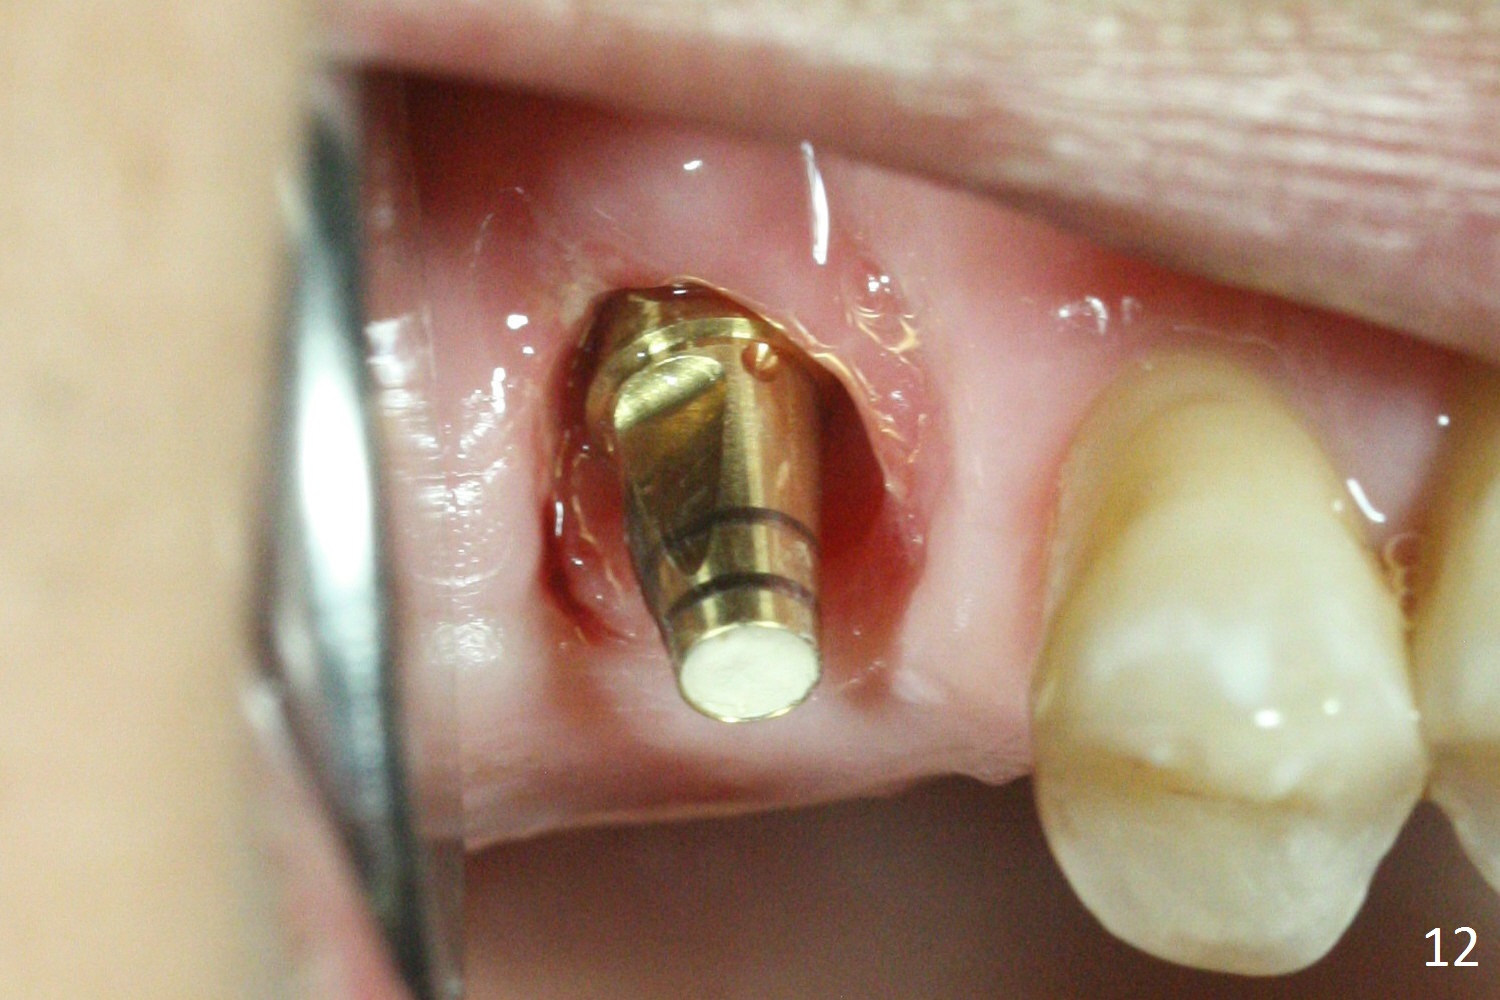

The buccal margin remains supragingival (Fig.10), while the palatal one subgingival 1.5 months postop (Fig.11 P). The abutment is changed to 4.8x7(3) mm (Fig.12). A provisional is fabricated to keep the palatal space for easy impression later on. With the smaller abutment and less tension, the buccal gingiva is expected to grow more coronal to reduce recession.